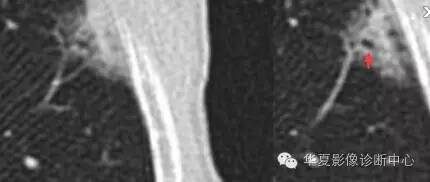

胸膜牵拉

结果自然就倾向于癌

磨玻璃结节良恶性影像分析策略磨玻璃结节良恶性影像分析策略 这个按常规看到血管由凹陷处进去常规95%考虑癌,可是这里却不是

除非说这里GGO边缘稍模糊一些

宽基底与胸膜相连

近端有模糊的高密度影